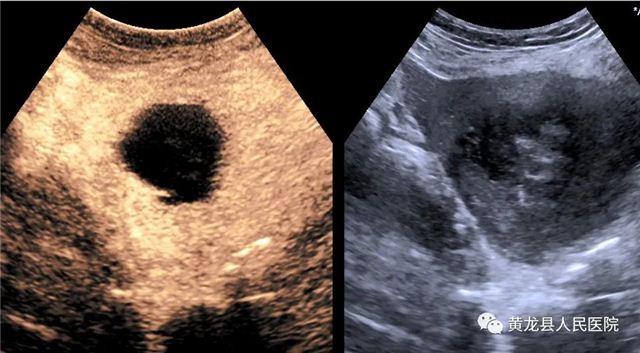

子宫肌瘤术前造影

子宫肌瘤术后造影